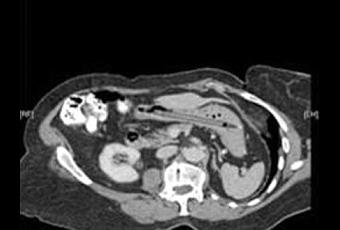

Source: BMJ Case Reports 2011 doi:10.1136/bcr.10.2011.5001An incidental finding of a gastric foreign body 25 years after ingestion.